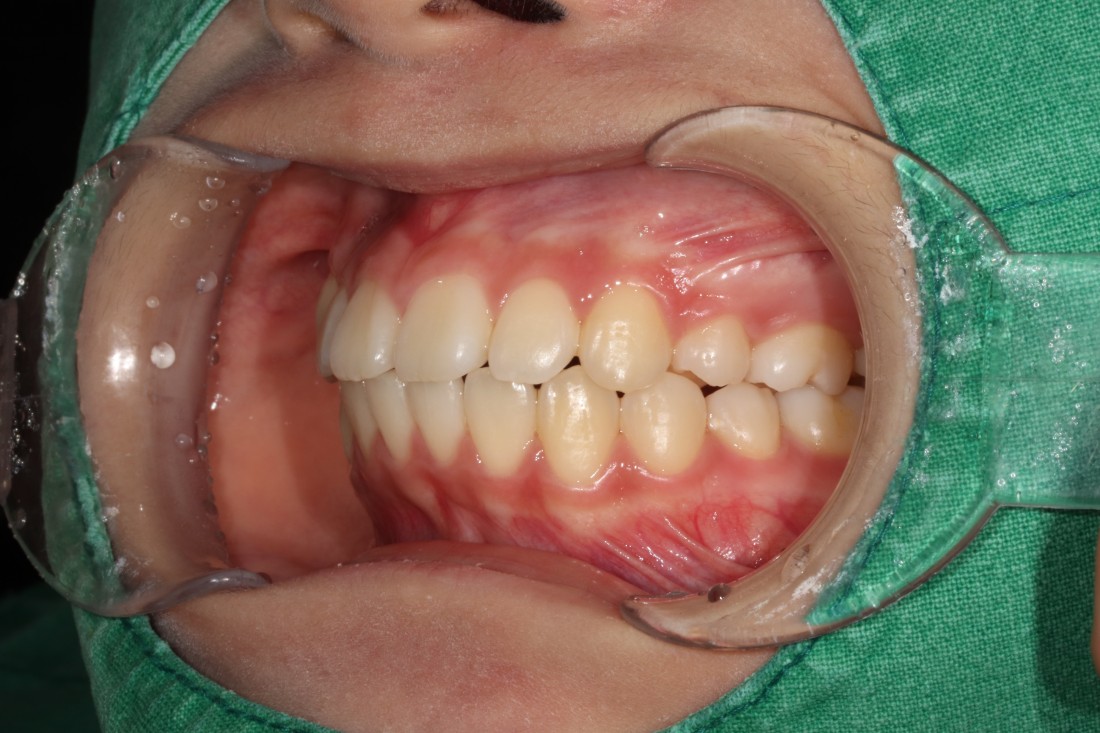

발치교정은 환자의 얼굴 균형을

맞추는 것이 핵심입니다.

잇몸이나 턱뼈 문제로

치아발치가 필요한 경우도 있기 때문에

발치교정의 핵심은

바로 '교정전문의의 실력' 이라고 할 수 있습니다.

많은 케이스를 다뤄본 의사가

가장 잘 하는 의사가 될 수 밖에 없기에

20년 넘는 교정진료 경험을 가진

광주 발치교정 치과의 교정전문의 진료로

믿을 수 있는 발치교정을 완성합니다.